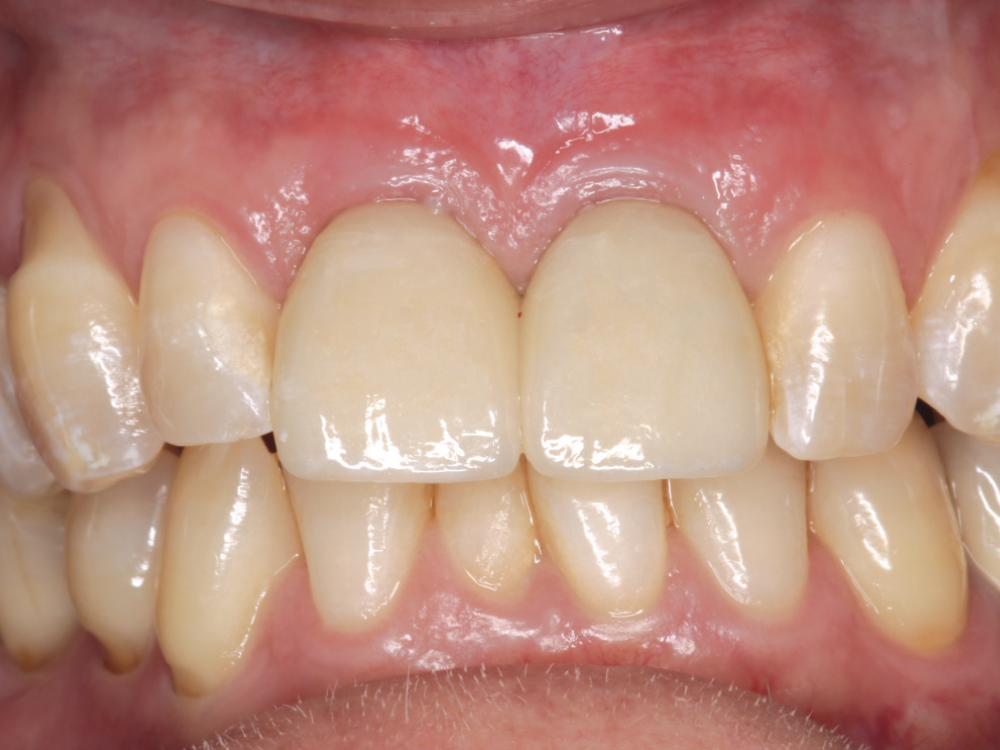

Endodontically treated tooth

Teeth needing extraction

After taking care to atraumatically remove the central incisors while avoiding damage to the buccal plate, two 3.5-mm-diameter Hahn Tapered Implants were placed into the extraction sockets. The pronounced thread design of the implants helped maintain proper position against the palatal wall during placement. The gaps between the implants and the extraction sockets were filled with Newport Biologics™ Mineralized Cortico/Cancellous Allograft Blend (Glidewell Direct).

Screw-retained crowns

Fixed teeth in a day

The Hahn implants achieved high primary stability, allowing for immediate provisionalization. Temporary screw-retained crowns were fabricated chairside and connected to the implants, providing the patient with fixed “teeth in a day” that would help facilitate an esthetic outcome by sculpting the gingival tissue during healing.